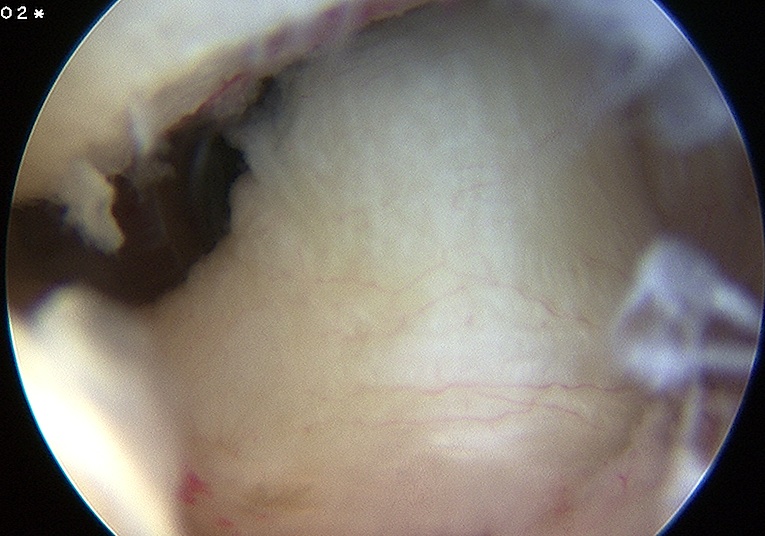

Abnormal

Isolated HAGL